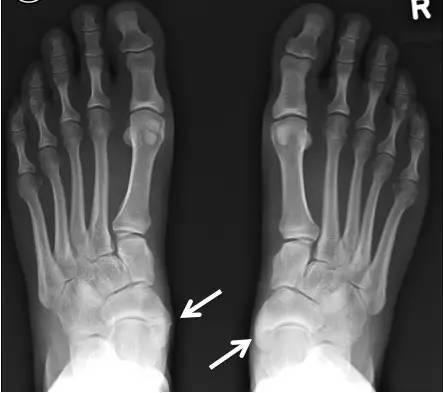

副舟骨和扁平足之间有很大关系。

一方面,改变胫骨后肌的发力方式,使前足内收足弓降低。另一方面,当足内翻时会撞击内踝,为缓解疼痛患者会采取足外翻的姿势,进一步引起足弓降低。

儿童如果存在平足,在骨化时副舟骨会向下向内侧移位。

当发生足副舟骨疼痛时,首先要拍X光确诊,并确定分型。